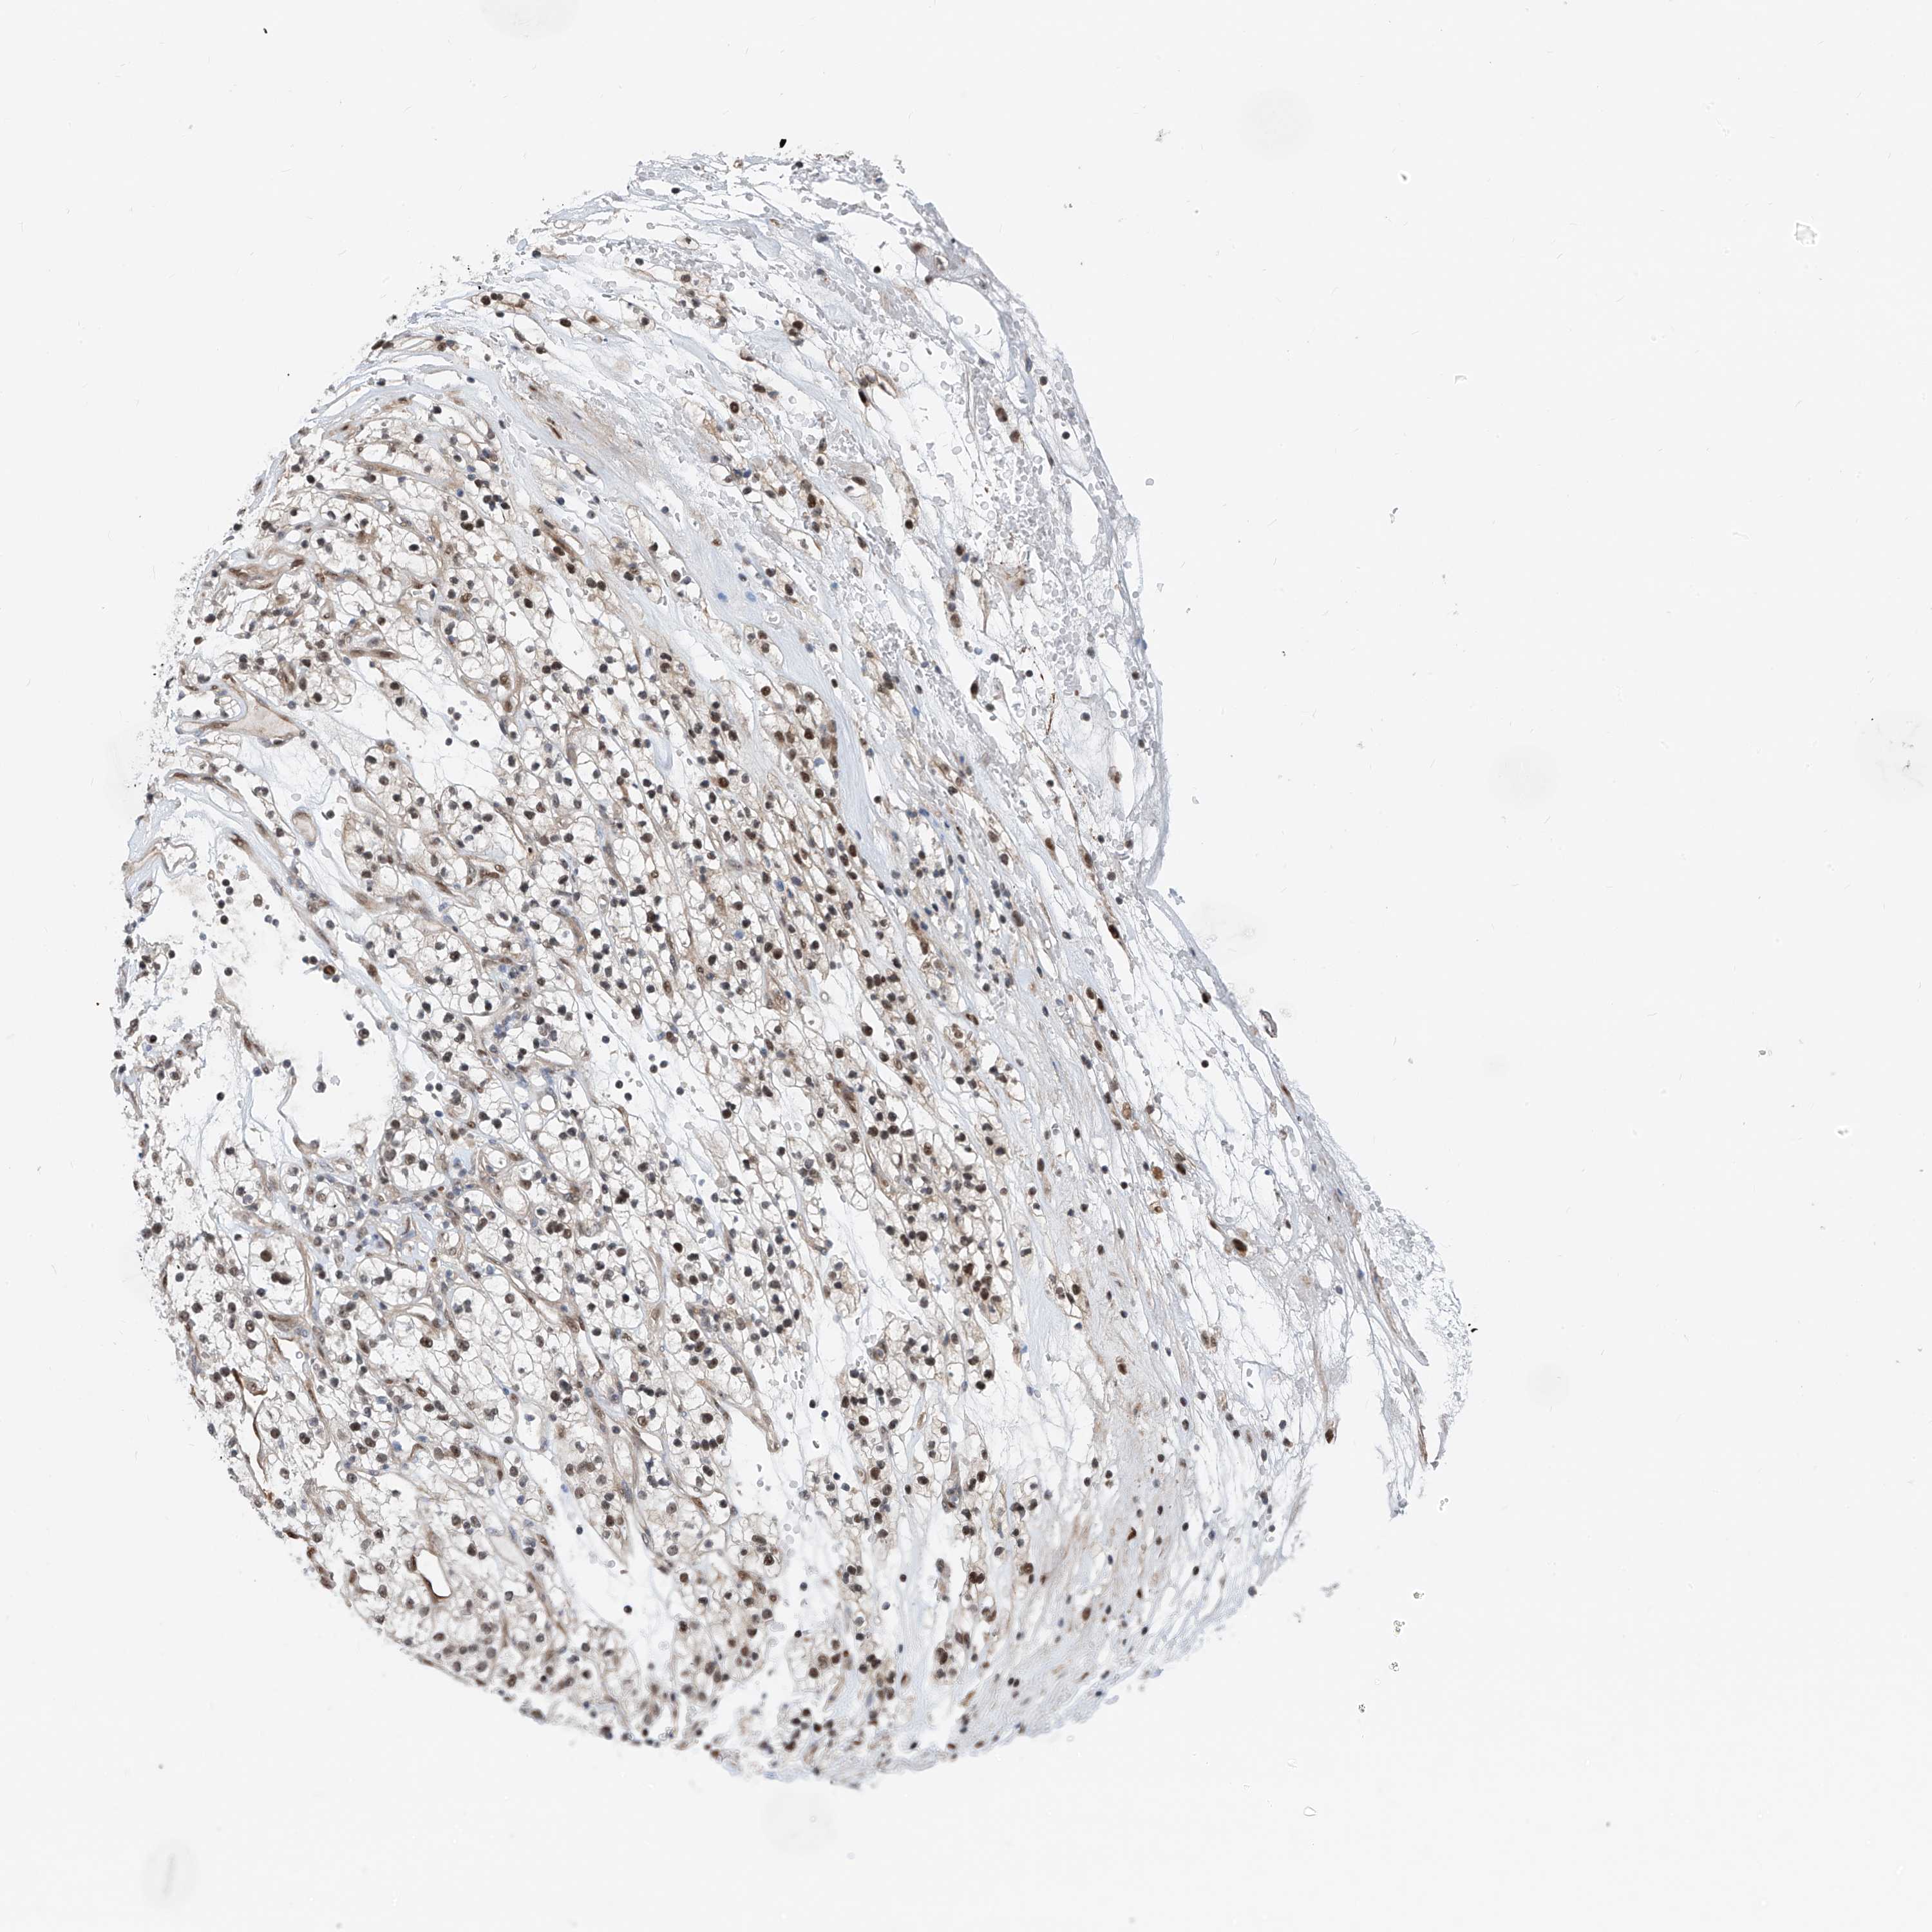

KIDNEY RENAL CLEAR CELL CARCINOMA (VALIDATION) - Interactive survival scatter ploti

The Survival Scatter plot shows the clinical status (i.e. dead or alive) for all individuals in the patient cohort, based on the same data that underlies the corresponding Kaplan-Meier plots. Patients that are alive at last time for follow-up are shown in blue and patients who have died during the study are shown in red.

The x-axis shows the expression levels (FPKM) of the investigated gene in the tumor tissue at the time of diagnosis. The y-axis shows the follow-up time after diagnosis (years). Both axes are complimented with kernel density curves demonstrating the data density over the axes. The top density plot shows the expression levels (FPKM) distribution among dead (red) and alive patients (blue). The right density plot shows the data density of the survived years of dead patients with high and low expression levels respectively, stratified using the cutoff indicated by the vertical dashed line through the Survival Scatter plot. This cutoff is automatically defined based on the FPKM cutoff that minimizes the p-score. The cutoff can be changed by dragging the vertical line or by entering a cutoff value in the square labeled "Current cut-off".

Under the Survival Scatter plot the p-score landscape (black curve; left axis) is shown together with dead median separation (red curve; right axis). Dead median separation is the difference in median mRNA expression between patients who have died with high and low expression, respectively. It is calculated as follows: median FPKM expression of dead patients with high expression - median FPKM expression of dead patients with low expression. This is intended to aid the user in visually exploring custom cutoffs and the associated p-scores and dead median separation.

Individual patient data is displayed and can be filtered by clicking on one or more of the category buttons on the top of the page. Categories describing expression level and patient information include: high, low, alive, dead, female, male and tumor stages. The scale of the x-axis can be toggled between linear and log-scale by clicking on the "x log" button. Mouse-over function shows TCGA ID, patient information and mRNA expression (FPKM) for each patient.

& Survival analysisi

Kaplan-Meier plots summarize results from analysis of correlation between mRNA expression level and patient survival. Patients were divided based on level of expression into one of the two groups "low" (under cut off) or "high" (over cut off). X-axis shows time for survival (years) and y-axis shows the probability of survival, where 1.0 corresponds to 100 percent.

RBP7 is validated prognostic, high expression is favorable in Kidney Renal Clear Cell Carcinoma (validation)

Best expression cut offi

Based on the FPKM value of each gene, patients were classified into two groups and association between prognosis (survival) and gene expression (FPKM) was examined. The best expression cut-off refers the FPKM value that yields maximal difference with regard to survival between the two groups at the lowest log-rank P-value. Best expression cut-off was selected based on survival analysis .

When clicking on this number, the vertical dashed line indicating cut-off, the interactive survival plot, and the Kaplan-Meier curve will be adjusted to show results based on the best expression cut-off.

: 43.39

TCGA RNA samplesi

RNA-seq data is reported as average FPKM (number Fragments Per Kilobase of exon per Million reads), generated by the The Cancer Genome Atlas (TCGA) .

Normal distribution across the dataset is visualized with box plots, shown as median and 25th and 75th percentiles. Points are displayed as outliers if they are above or below 1.5 times the interquartile range. FPKM values of the individual samples are presented next to the box plot.

Average pTPM 64.7

Number of samples 100